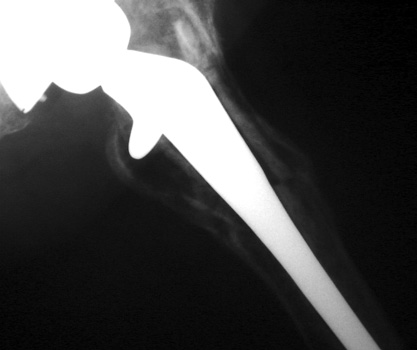

No prior studies available. Abnormally widened interfaces surrounding entire cement mantle of femoral component, consistent with loosening.

No prior studies available. Abnormally widened interfaces about femoral component at Gruen zones 1, 6, and 7. Osteolysis at Gruen zone 5 with marked thinning of femoral cortex placing patient at risk for pathologic fracture.

SUBSIDENCE - loose femoral prosthesis with interface widening,

osteolysis Gruen zone 6, cement fracture left femoral component

and osteolysis, with femoral component in valgus.